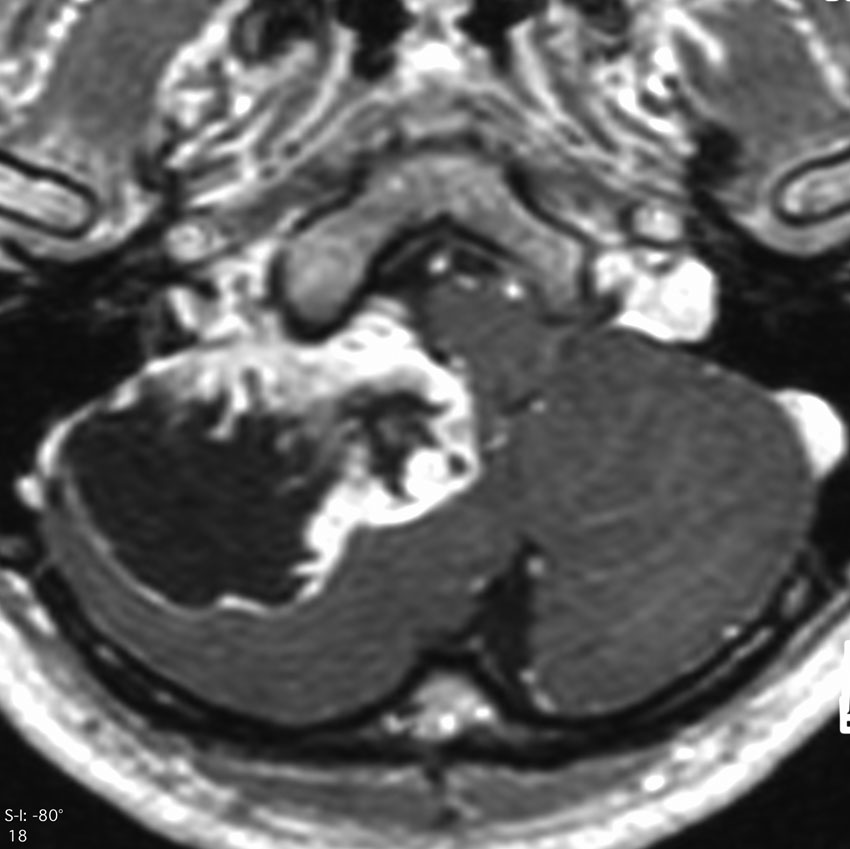

症例:頸静脈孔から頭蓋内へのもの

頸静脈孔を中心に頭蓋底骨の破壊 erosionがみられます。小脳延髄角部に進展して延髄を圧迫しています。聴神経を圧迫して聴力低下で発見された,迷走神経鞘腫です。頸静脈孔内発生のものは脳槽内の迷走神経根から腫瘍を剥離することができます。

手術直後のMRIです。頸静脈孔より深い位置にある腫瘍まで摘出しようとすると,舌咽,迷走,副神経を損傷しますから,最深部の部分だけ残して摘出しました。

手術後14年が経過しますが,無治療で残存腫瘍は縮小しました。術後神経鞘腫の自然経過ではよく観られることです。

ですから,無理して全摘出しない。